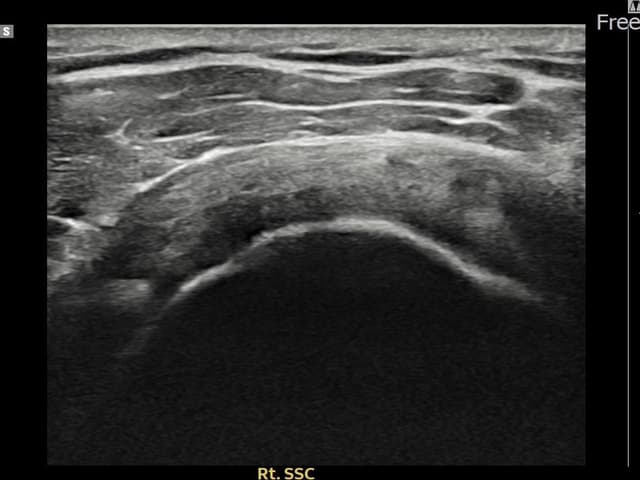

[経過期間: 24.03.04~24.05.10]

[縫縮術] 超音波検査にて右 견갑하근건 関節面側部分断裂(7mm × 3mm (腱厚の約28%欠損))を確認。縫縮術施行後、腱の連続性が回復し、日常生活に復帰されました。